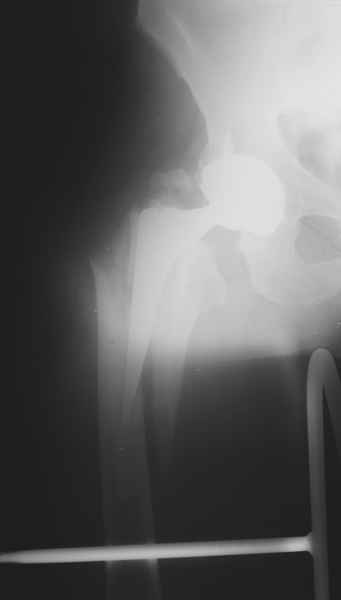

Произведено закрытое удлинение ножки эндопротеза с помощью ретроградного интрамедуллярного стержня. Продолжительность операции 3 часа. Два из них закрытое восстановление длины бедра диистрактором

таз-бедро.

новые снимки

Пациента удалось осмотреть недавно. Достигнутый результат сохраняется. Перелом бедра сросся. Конечность опорная и безболезненная, ходит без трости. Ножка, похоже, реинтегрировалась, как и надеялись. Снимки и фото в приложении. Комментарии приветствуются.

Надо ли что-то делать дальше, как полагаете? Убрать винты? Убрать "удлинитель ножки"? Или оставить все, как есть? Спасибо заранее.